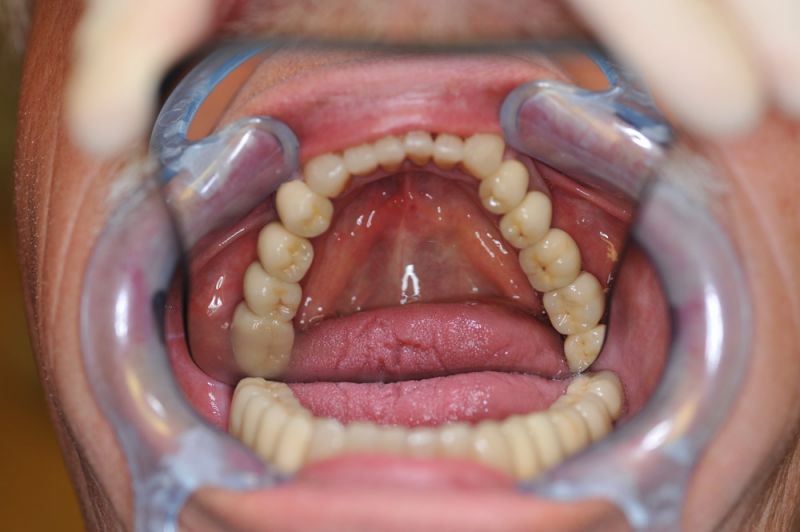

Patient aus der Region Ostholstein zur Abschlussuntersuchung

Jede Rekonstruktion findet einmal ein Ende. So auch diese. Der Patient ist zufrieden, die Arbeit sieht gut aus!

Wie gehabt: Vierteljährlicher Recall, um die Arbeit möglichst lange zu erhalten.

Der Patient betreibt eine gute Mundhygiene. Der Patient ist in einem sehr guten, vitalen Zustand und hat jetzt noch einmal die Substanz geschaffen, um mit dieser Versorgung möglichst bis ans Lebensende zu kommen.